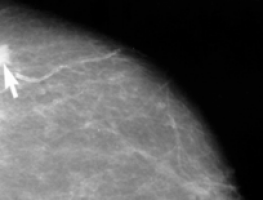

Researchers at the Cancer Research UK Cambridge Research Institute have built a computer system that automatically analyses microscopy images of hundreds of breast cancer samples.

The new approach looks at the makeup of the cells within a tumour, normally undertaken by a pathologist looking down a microscope, and combines these images with the key genetic changes that are crucial for the development of breast cancer.